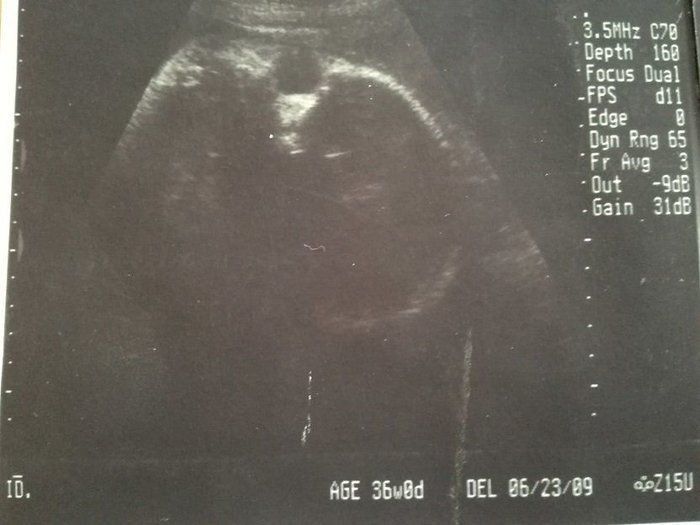

2度“逆子”になった胎児はもう小学生!子どもと共に読み返した当時の日記&エコー画像 -

「背骨!足骨!ホントに人間がいる!」エコー画像を見る度、ゆっくり親になっていく私たち -